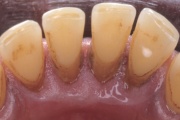

- puudulik suuhügieen (5)

- igemepealne hambakivi (5)

- igemealune hambakivi (4)

- igemepiir on taandunud (3)